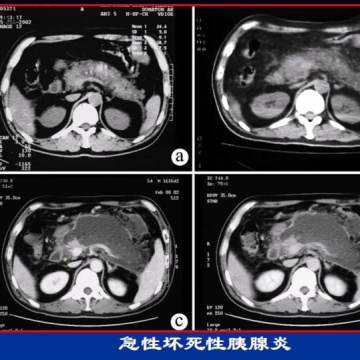

急性胰腺炎(acute pancreatitis,AP)是多种病因导致胰腺组织自身消化所致的胰腺水肿、出血及坏死等炎症性损伤。以急性上腹痛及血淀粉酶或脂肪酶升高为特点。胰腺在很长一段时间不被认知,古希腊人在公元前100年左右将胰腺命名为pancreas,意思是“全部是肉”。中国医典在《难经一四十二难》中称之为“散膏”,在《本草纲目》中称之为“肾脂”。1652年,丹麦解剖学家尼古拉斯·杜尔(Nicholas Tulp)首次对急性胰腺炎进行了相关临床描述,直至19世纪末20世纪初,人们对急性胰腺炎的认识才逐步浮现。急性胰腺炎全世界每年的发病率为13/10万~45/10万,中国20年间发病率由0.19%上升至0.71%,80%~85%的患者为轻症急性胰腺炎。急性胰腺炎的致病原因较多,胆石症、酒精仍是最常见病因,约占70%以上。随着中国人民生活水平的提高和饮食习惯的改变,由高脂血症诱发的AP逐年增多,占10%左右,在妊娠妇女中甚至高达50%。其他病因约占10%。发生AP的诱因主要有暴饮暴食、油腻(高脂肪)饮食、酗酒等其他因素,它们会诱发胆囊结石排入胆道,引起乳头括约肌(Oddi括约肌)痉挛,增加血液中甲状腺球蛋白(thyrobolulin,TG)水平,促进胰液大量分泌等。妊娠、肥胖、吸烟、糖尿病患者是AP发病的危险因素。急性腹痛是大多数急性胰腺炎病人的首发症状,常较剧烈,多位于中左上腹甚至全腹,部分患者腹痛向背部放射,病人病初可伴有恶心、呕吐,轻度发热。常见体征:中上腹压痛,肠鸣音减少,轻度脱水貌。急性胰腺炎以寻找并去除病因、控制炎症为治疗目的,应尽可能采取内科及微创治疗。临床实践表明,重症急性胰腺炎时手术创伤将加重全身炎症反应,增加死亡率。如诊断为胆源性AP,应尽可能在本次住院期间完成内镜治疗或在康复后择期行胆囊切除术,避免今后复发。胰腺局部并发症如有明显临床症状的胰腺假性囊肿、胰腺脓肿及左侧门静脉高压,可通过内镜或外科手术治疗。急性胰腺炎轻症病人常在1周左右康复,不留后遗症。中重症急性胰腺炎患者预后较好,重症急性胰腺炎患者病死率较高,为34%~55%,伴有多系统器官功能衰竭者,病死率几乎达100%。